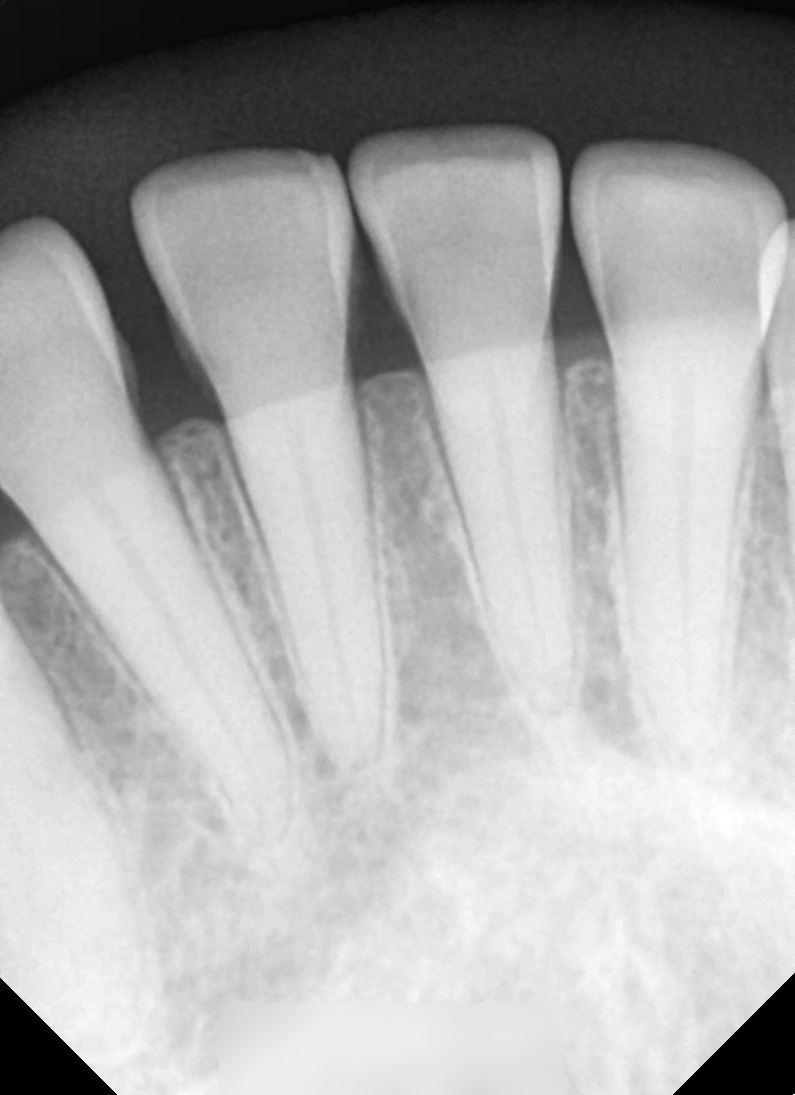

전체 파노라마 사진을 통해 확인해볼 수 있습니다.

다행히 크게 벌어짐이 있지 않으며

오밀조밀 잘 붙어있습니다.

아래 앞니 쪽만 개선이 필요합니다.

하악 전치부의 간격에 의하여

Space가 눈에 띄게 도드라집니다.

특히 41번과 42번에서의 간격이

넓은 편이었기에 진행되는 과정을 파악해

기간을 결정해야 될 것으로 사료됩니다.